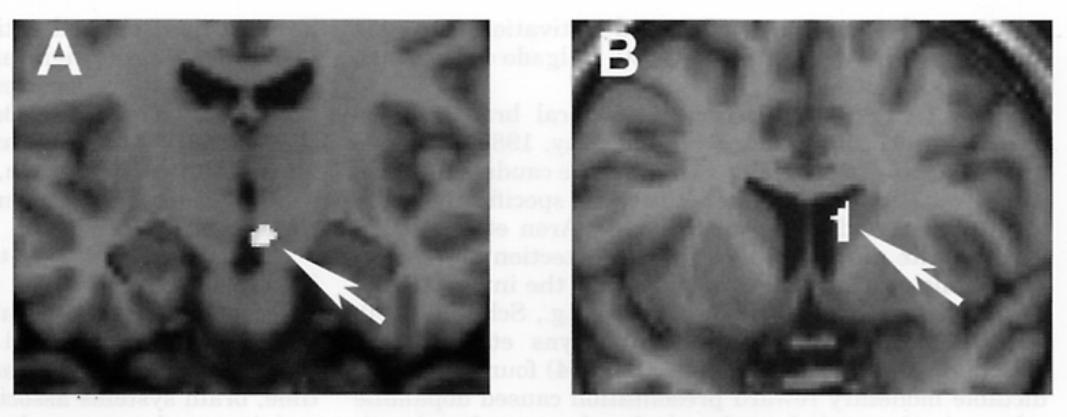

Это напоминает состояние абстиненции (синдром отмены), в котором находится человек с зависимостью, когда перестает принимать стимуляторы. Исследование, проведенное все той же Хелен Фишер и ее коллегами в 2010 году, , что после недавнего расставания у людей, тяжело переживающих разрыв, в системе вознаграждения активируются те же зоны, что и употребляющих кокаин.